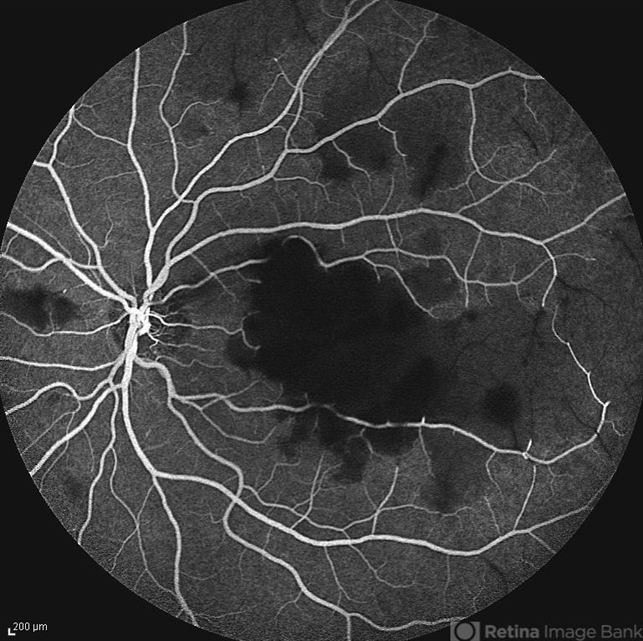

- retinal vasculitis, capillary nonperfusion

- Naghmeh Nozhat, Negah Eye Center, Tehran

- Imaging device

- Heidelberg Spectralis

- Mid- phase fluorescein angiogram of the left eye of a 28-year-old woman with acute drop of vision due to occlusive retinal vasculitis leading to extensive capillary nonperfusion and macular infarction.